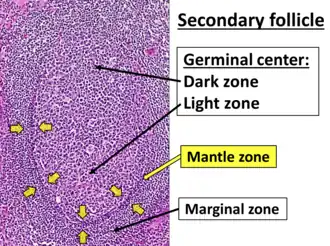

A lymph node is divided into compartments called nodules (or lobules), each consisting of a region of cortex with combined follicle B cells, a paracortex of T cells, and a part of the nodule in the medulla.[17] The substance of a lymph node is divided into the outer cortex and the inner medulla.[4] The cortex of a lymph node is the outer portion of the node, underneath the capsule and the subcapsular sinus.[17] It has an outer part and a deeper part known as the paracortex.[17] The outer cortex consists of groups of mainly inactivated B cells called follicles.[5] When activated, these may develop into what is called a germinal center.[5] The deeper paracortex mainly consists of the T cells.[5] Here the T-cells mainly interact with dendritic cells, and the reticular network is dense.[18]

In the lymphatic system a lymph node is a secondary lymphoid organ.[5] Lymph nodes contain lymphocytes, a type of white blood cell, and are primarily made up of B cells and T cells.[5] B cells are mainly found in the outer cortex where they are clustered together as follicular B cells in lymphoid follicles, and T cells and dendritic cells are mainly found in the paracortex.[19]

As part of the reticular network, there are follicular dendritic cells in the B cell follicle and fibroblastic reticular cells in the T cell cortex. The reticular network provides structural support and a surface for adhesion of the dendritic cells, macrophages and lymphocytes. It also allows exchange of material with blood through the high endothelial venules and provides the growth and regulatory factors necessary for activation and maturation of immune cells.[21]